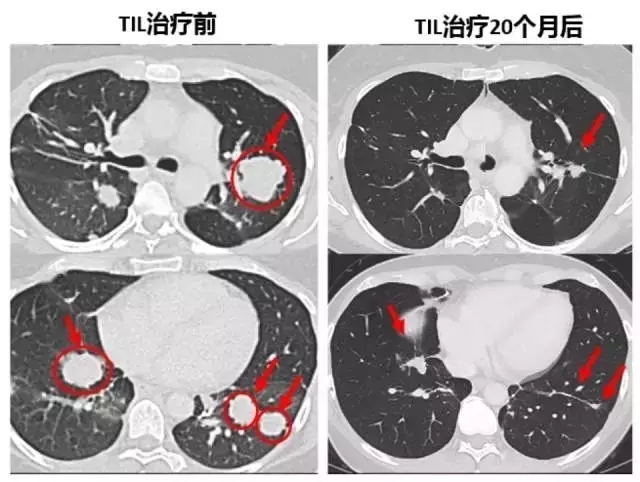

下面的对照图可以非常明显看到,第二次治疗前肺部布满的肿瘤,包括一些个头非常大的,第二次TIL治疗20个月后复查,这些肿瘤都非常显著的缩小了,现在她已经成为了十年幸存者!